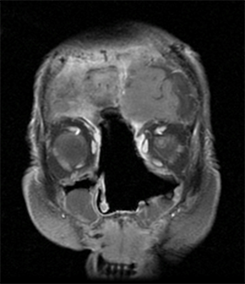

In this study we aim to assess whether patients undergoing resection for anterior skull base tumours develop ENS. As part of their oncological procedure these patients are often left with a true ‘empty nose’ with not only loss of turbinate volume and ethmoid/sphenoidotomy but also significant loss of nasal mucosa. An example of this is demonstrated in Figure 1